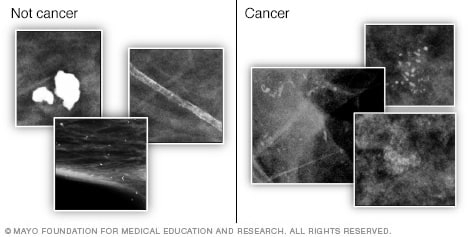

They appear as white spots or flecks on a mammogram but can't be felt during a breast exam. A new group has formed. For women treated for breast cancer in the past, calcifications may also be due.

There are numerous causes for calcium deposits in the breasts, including: But, japanese food natto has the ability to decalcify and maintain uniform level of calcium throughout the body and parts. Breast calcifications. california pacific medical center: